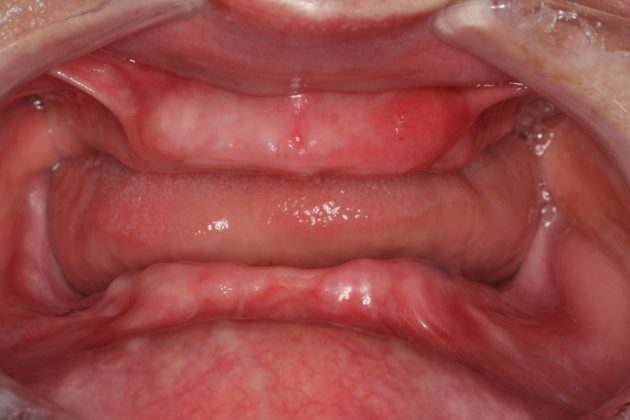

在传统种植牙手术中,医生没有精确的仪器设备判断缺牙位牙槽骨、咬合关系,多借助二维及人工目测的方式,其次,医生也缺乏将正确的诊断和合理的种植方案一丝不差到患者口腔的手段,诸此种种,导致传统种植牙手术只能凭医生的经验来完成,这种以"盲种"的方式,无法对更复杂的缺牙情况进行有效处理,比如半口全口缺牙、咬合关系重建等。

MAC精确种牙可通过动态咬合模拟,完成咬合关系重建

七旬老人在麦芽口腔实现5颗钉种半口